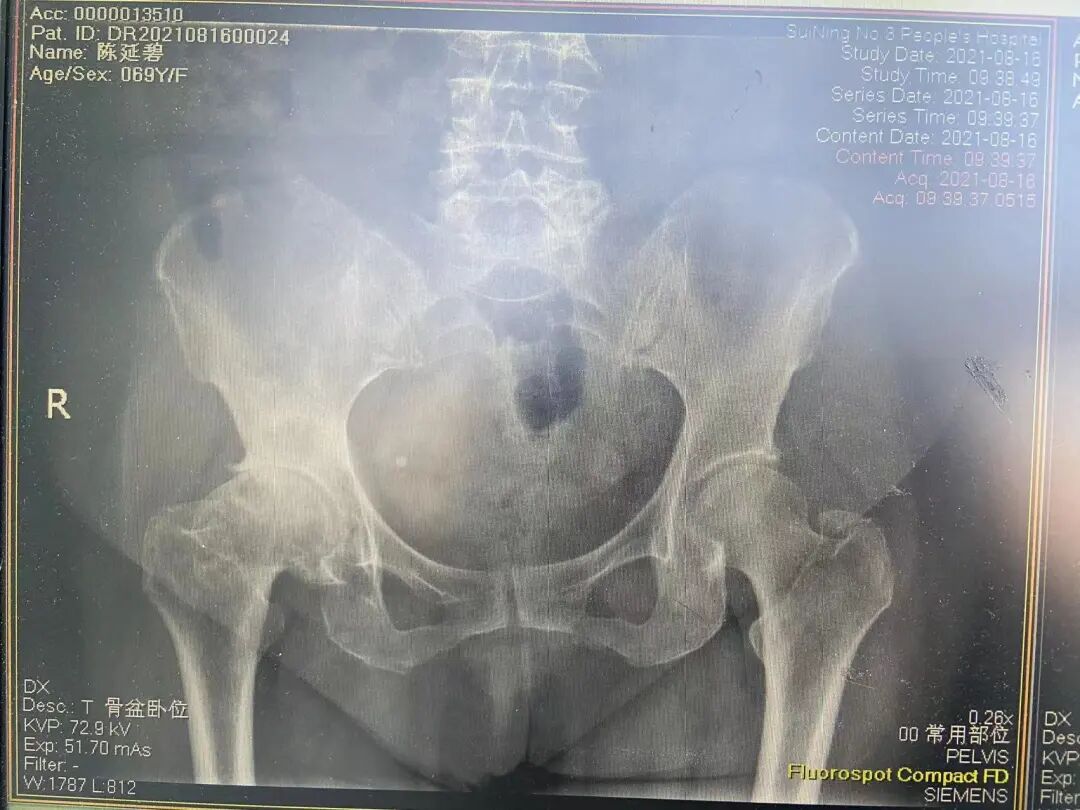

右侧股骨头坏死

右髋关节置换术